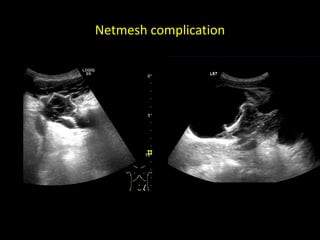

Netmesh

with post-operative fluid collections

Netmesh complication

Pain from tag fixation of a netmesh

Pain from tagfixation of a netmesh